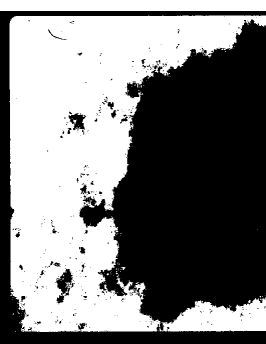

In many dermoscopic images, the lesion can be roughly separated from the background skin using a grayscale thresholding method applied to the blue channel [8, 9]. While there are a number of thresholding methods that perform well in general, the effectiveness of a method strongly depends on the statistical characteristics of the image [18]. Fig. 2 illustrates this phenomenon111The frame of this image is left intact for visualization purposes.. Here, methods 2(d), 2(e), and 2(g) perform quite well. In contrast, methods 2(c) and 2(h) underestimate the optimal threshold, whereas method 2(f) overestimates the optimal threshold. Although method 2(c) is the most popular thresholding algorithm in the literature [25], for this particular image, it performs the second worst.

Refer to caption

(a) Original image

(b) Blue channel

(c) Otsu’s method [19] (T = 137)

(d) Kapur et al.’s method [20] (T = 178)

(e) Huang & Wang’s method [21] (T = 183)

(f) Yen et al.’s method [22] (T = 200)

(g) Sahoo et al.’s method [23] (T = 179)

(h) Li & Tam’s method [24] (T = 59)

Figure 2: Comparison of various thresholding methods (T: threshold)